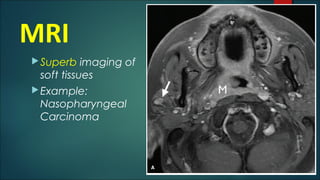

MRI

Superb imaging of

soft tissues

Example:

Nasopharyngeal

Carcinoma

• #6 MRI is utilized for visualizing soft tissue pathology owing to superior discrimination. An application would be in viewing an nasopharyngeal mass.